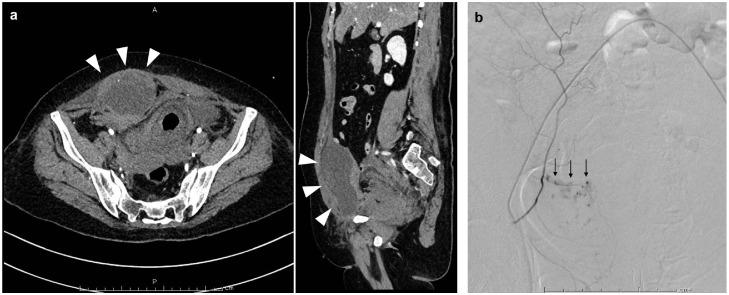

A non-traumatic abdominal wall hematoma is rare, and occurs occasionally due to coughing, physical activity, or antithrombotic/anticoagulant therapy. The condition is usually unilateral; however, rare bilateral cases have been reported. Here, we report a rare case of a non-traumatic bilateral rectus sheath hematoma. The patient was a 60-year-old woman who was urgently admitted to our hospital due to the occurrence of pneumonia during postoperative chemotherapy for breast cancer. Because she exhibited disseminated intravascular coagulation, a therapy with antibacterial agents, thrombomodulin alpha, and catecholamines was initiated. During hospitalization, hemorrhagic shock due to hematomas in both rectus abdominis muscles was observed without any discernible cause. Subsequent emergency angioembolization was successful, and abdominal computed tomography performed 3 months after the onset of the rectus sheath hematoma confirmed a reduction in the hematoma size.

摘要

非创伤性腹壁血肿较为罕见,偶尔因咳嗽、体力活动或抗血栓/抗凝治疗而发生。该病通常为单侧性;然而,也有罕见的双侧病例报道。在此,我们报告一例罕见的非创伤性双侧腹直肌鞘血肿病例。患者为一名60岁女性,因乳腺癌术后化疗期间发生肺炎而紧急入院。由于她出现了弥散性血管内凝血,遂开始使用抗菌药物、重组血栓调节蛋白α和儿茶酚胺进行治疗。住院期间,在无任何明显诱因的情况下,观察到双侧腹直肌出现血肿导致失血性休克。随后的急诊血管栓塞术取得成功,腹直肌鞘血肿发病3个月后进行的腹部计算机断层扫描证实血肿大小有所减小。